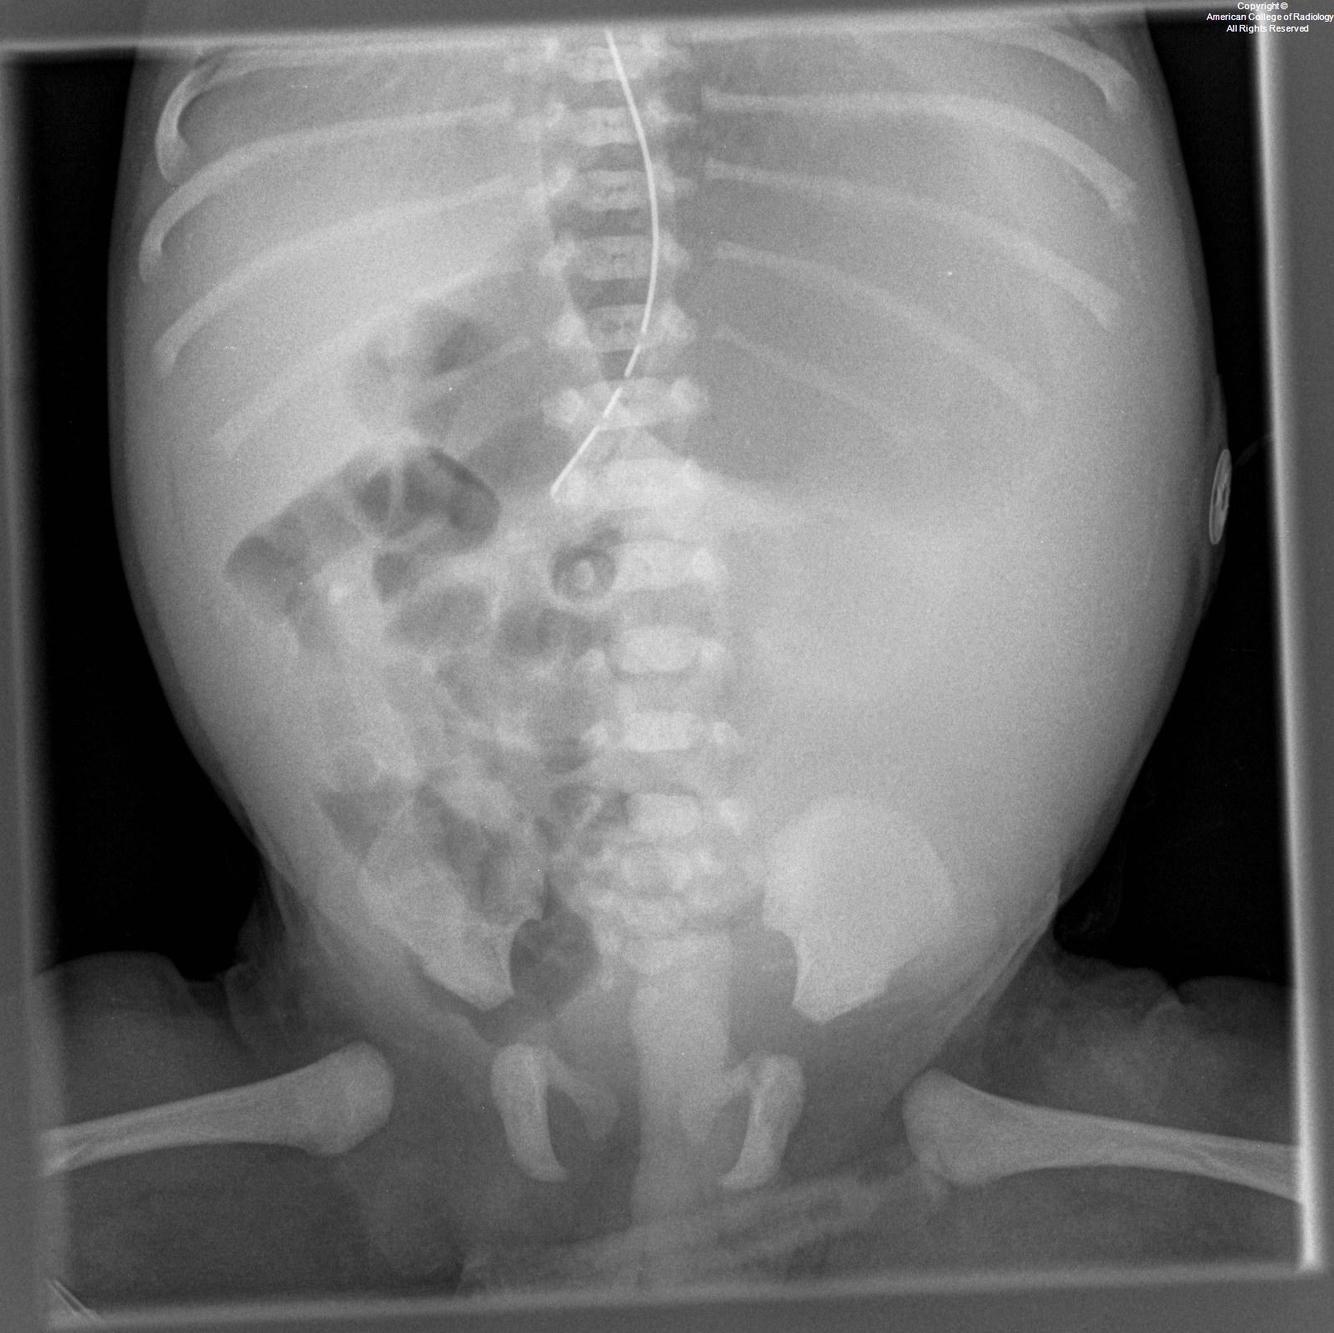

In-utero bowel perforation

from meconium

meconium peritonitis